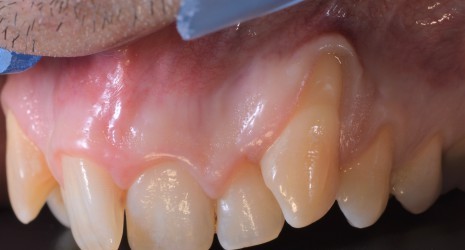

Cirugía Plástica de la encía

A menudo existen malformaciones o defectos adquiridos a lo largo de la vida en la encía de los que los pacientes pocas veces son conscientes. Estos incluyen sobre todo, retrocesos de la encía y ausencia de encía alrededor de los dientes. En casos muy avanzados pueden suponer un riesgo para la dentición.

Existen multitud de técnicas quirúrgicas como los injertos de paladar para solventar estos problemas.